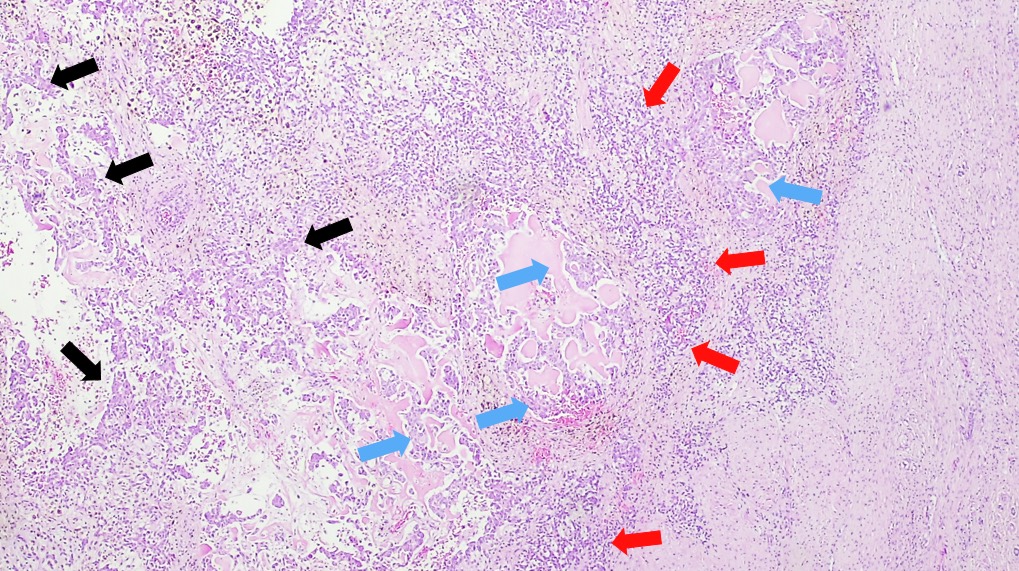

Microscopic (histologic) description

- Classified by the International Pediatric Liver Tumor Consensus Classification as epithelial or mixed epithelial and mesenchymal

- Epithelial hepatoblastoma may exhibit several patterns (alone or in combination): fetal, embryonal, small cell undifferentiated (SCUD), cholangioblastic and macrotrabecular (J Gastrointest Oncol 2018;9:326)

- Fetal pattern (Pediatr Dev Pathol 2020;23:79)

- Thin trabeculae or nests of small to medium sized cells resembling hepatocytes of the developing fetal liver

- Clear or finely granular cytoplasm with variable amount of glycogen and lipids

- Small round nucleus with indistinct nucleolus

- Foci of extramedullary hematopoiesis are usually present

- Typically has low mitotic activity, referred to as well differentiated hepatoblastoma

- A subset has increased mitotic activity, with decreased cytoplasmatic glycogen and pleomorphic nuclei, referred to as mitotically active hepatoblastoma

- Embryonal pattern (Pediatr Dev Pathol 2020;23:79)

- Resembles the developing liver at 6 - 8 weeks of gestation

- Solid nests or glandular / acinar morphology, with papillae and pseudorosettes

- Dark and granular cytoplasm without glycogen or lipids

- Enlarged nuclei with coarse chromatin, resembling blastemal cells

- Extramedullary hematopoiesis is usually absent

- Increased mitotic activity

- Small cell undifferentiated pattern (Pediatr Dev Pathol 2020;23:79)

- Solid sheets of discohesive small cells (small, round blue tumor)

- Abundant mitoses, apoptosis and necrosis

- Macrotrabecular pattern

- Thick trabeculae (5 - 12 cells thick)

- Trabeculae may be composed of fetal, embryonal, pleomorphic or hepatocellular carcinoma-like cells

- Mesenchymal pattern (Pediatr Dev Pathol 2020;23:79)

- Mature and immature fibrous tissue

- Osteoid or osteoid-like tissue (more abundant after chemotherapy)

- Hyaline cartilage

Microscopic (histologic) images